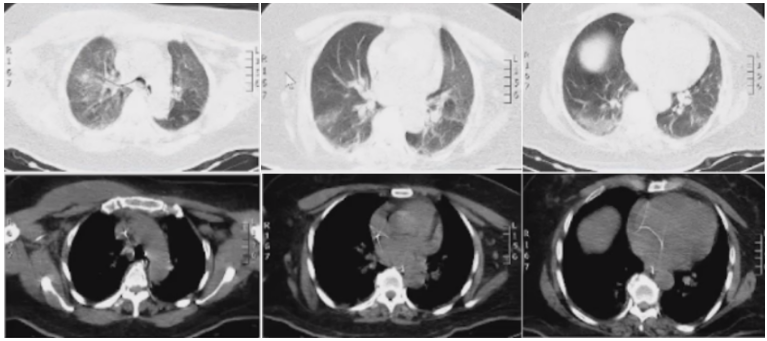

炎症指标:CRP 124 mg/L,ESR>140 mm/h,PCT 1.6 ng/ml。血气分析:pH 7.520,PaCO2 49.0 mmHg,PaO2 85.0 mmHg,cLac 0.8 mmol/L,cHCO3- 40.0 mmol/L,BE 15.7 mmol/L,SpO2 97%。肝肾功能电解质:ALT 41.0 U/L,AST 36.7 U/L,TP 68.4 g/L,ALB 32.9 g/L,GLO 35.5 g/L,BUN 28.9 mmol/L,Crea 236.0 μmol/L,Na 152.6 mmol/L,K 4.15 mmol/L,Cl 107.9 mmol/L。心肌酶学:LDH 316.5 U/L,CK 45.0 U/L,CK-MB 19.1 U/L,cTnT 29.74 pg/ml,BNP 1514 pg/ml。大小便常规、尿沉渣、凝血功能、乙丙肝、HIV、梅毒均未见明显异常。淋巴细胞亚群:T淋巴细胞绝对计数471个/μl(↓),CD4+T淋巴细胞绝对计数316个/μl(↓),CD8+T淋巴细胞绝对计数126个/μl(↓),NK细胞绝对计数44个/μl(↓)。免疫球蛋白:免疫球蛋白lgG 7.62 g/L(↓),免疫球蛋白lgA 3.32 g/L(↓),免疫球蛋白lgM 0.73 g/L(↓),免疫球蛋白lgE 7488.00 ng/ml(↑)。心脏彩超:二、三尖瓣轻度反流,左室收缩功能测值正常范围,射血分数63%。胸部CT(8月15日):双侧胸腔积液较前增多,右上肺可见实变影及磨玻璃影,少量小叶间隔增厚,病灶较前进展。

支气管镜检查(8月14日):镜下见双侧支气管黏膜充血肿胀,未见明显分泌物(图5)。细菌+真菌培养、GM试验均阴性。多联病原体核酸检测:鲍曼不动杆菌、肺炎克雷伯杆菌。8月16日痰培养示鲍曼不动杆菌,两次血培养均阴性。